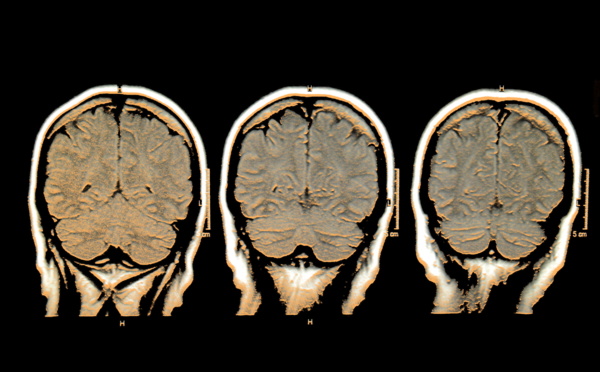

Extraña actividad neuronal en cerebros con “electroencefalograma plano” - 23/09/2013

Científicos de diversos centros de investigación han detectado una actividad neuronal hasta ahora desconocida en cerebros en “muerte cerebral”. Se trata de unas oscilaciones generadas en el hipocampo, que es la parte del cerebro responsable de la memoria y de los procesos de aprendizaje, que eran transmitidas a la parte principal del cerebro, la corteza. El hallazgo podría tener aplicaciones terapéuticas.